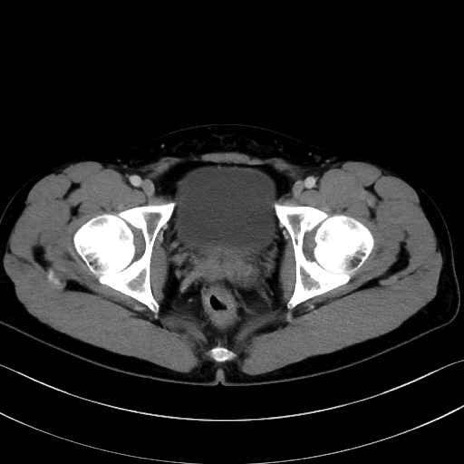

梨状筋(piriformis muscle) のCT画像の解剖

内閉鎖筋 (Obturator internus)

外閉鎖筋 (Obturator externus)